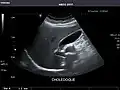

Gallbladder